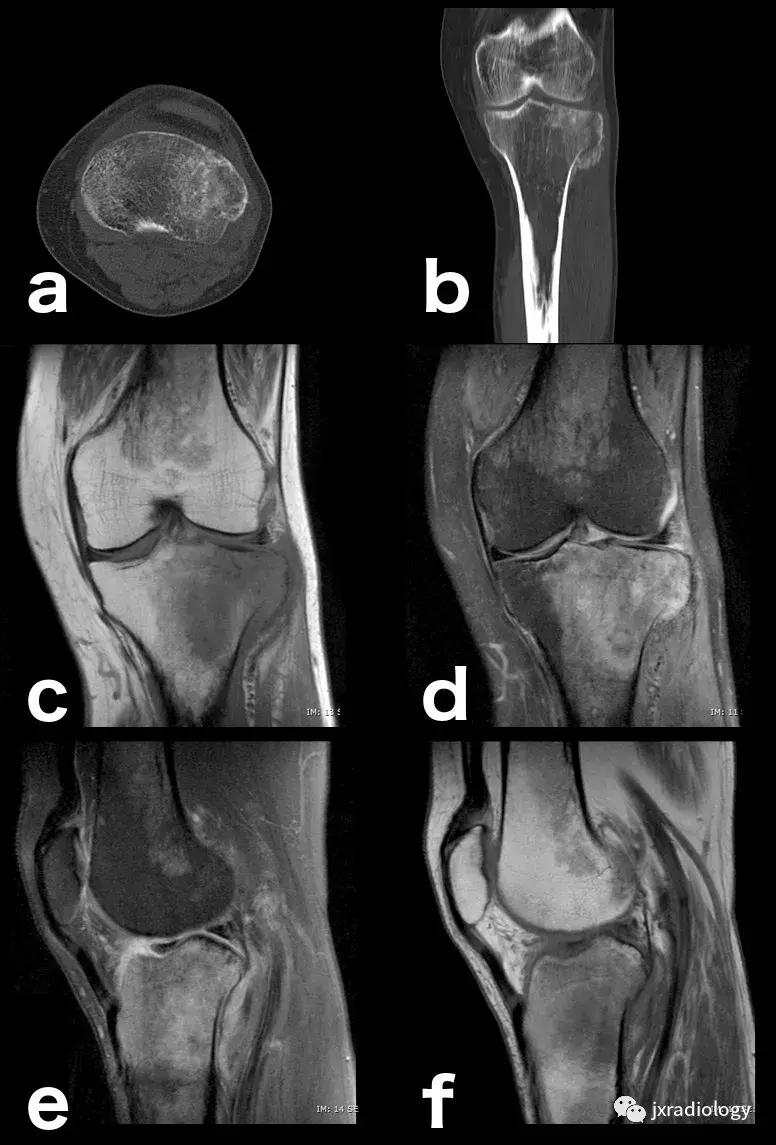

图14:创伤性骨水肿,肉眼可见的亚急性骨折:即使CT扫描(a,b)上的骨折线稍不明显,MRI上骨髓水肿也指出病变(c,d,e,f)。

图24:骨样骨瘤:在这些良性肿瘤中,水肿可以继发于前列腺素E2引起的炎症反应(a,b:横断位和冠状CT扫描; c,d:横断位T1-WI和冠状位PD-FS-WI)。